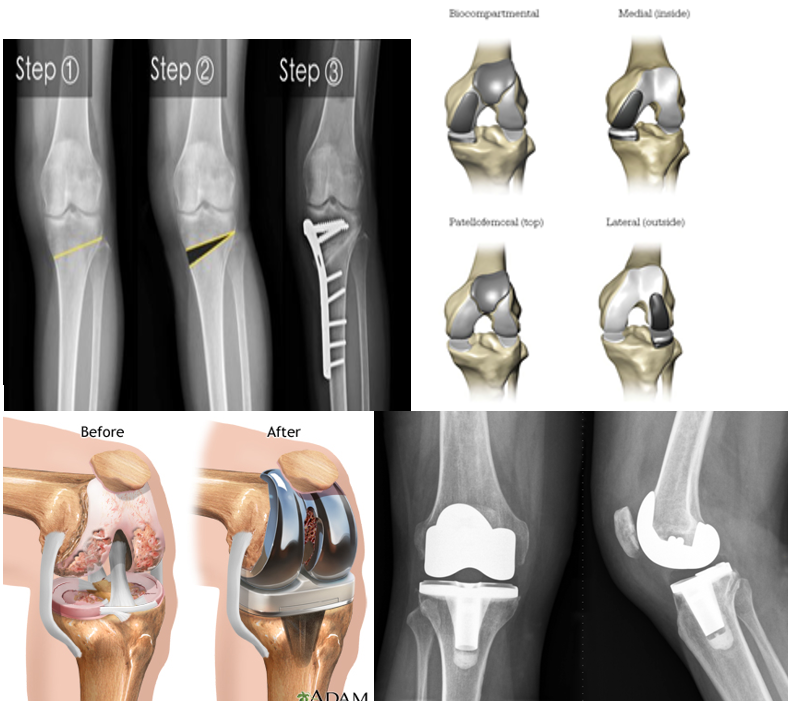

Q

Degenerative Joint Disease/Arthritis Operative Treatment

• High tibial ______

• Younger patients with isolated medial disease (uncommon)

• ____compartmental arthroplasty (much less common than TKA)

• _____ Knee Arthroplasty

• Approaching 1 million per year in the US!

• Projected 855% increase by 2050…(will it bankrupt the system!?)

A

• High tibial osteotomy

• Unicompartmental arthroplasty (much less common than TKA)

• Total Knee Arthroplasty

22

Surgical Steps

• Meet the patient in the ___-op holding area

• ___ the leg

• N______ and a_____ meets with the patient as well. This is almost always the first (and only) time the patient meets their anesthesiologist

• To OR

• Anesthesia (usually s_____)

• Position (leg t______)

• Prep/drape

• Time-____

• Incision, cut distal ______, cut proximal _____ (both perpendicular to the mechanical axis of the leg, either using mechanical jigs or computer navigation).

• Meet the patient in the pre-op holding area

• Mark the leg

• Nursing and anesthesia meets with the patient as well. This is almost always the first (and only) time the patient meets their anesthesiologist

• Anesthesia (usually spinal)

• Position (leg tourniquet)

• Time-out

• Incision, cut distal femur, cut proximal tibia (both perpendicular to the mechanical axis of the leg, either using mechanical jigs or computer navigation).

23

Finishing Cuts, Trials

• St______ in flexion, extension, midflexion

• Full extension, flexion to ~____ degrees

• Regardless _____ ROM is best predictor of post-op…

• Remove trials

• Wash

• Ce_____ in real components

• Close

• R_____ room

• Stability in flexion, extension, midflexion

• Full extension, flexion to ~120

• Regardless pre-op ROM is best predictor of post-op…

• Cement in real components

• Recovery room

24